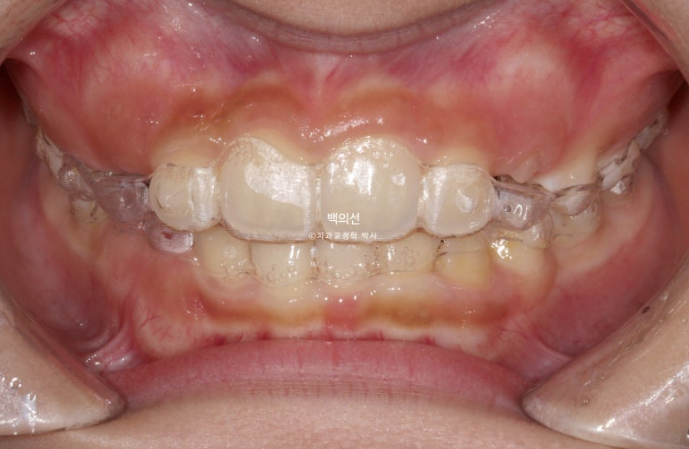

23.07

교정치료를 위해 온 만 9세 어린이입니다.

부모님이 클리피씨 철사 교정을 한 경험이 있어서 아이에게는 인비절라인 퍼스트 투명교정을 시키고 싶어

내원하셨습니다.

부모님이 고치고 싶은 것은 앞니가 깊게 물리는 과개교합

아래 앞니가 보이지 않을 정도의 심한 과개교합입니다.

앞니 돌출이 있으며

악궁전반부가 좁습니다.

아래도 마찬가지로 악궁확장이 필요합니다.

이 날 공간이 부족하여 앞니가 삐뚤게 나왔고 곧 나올 송곳니는 공간이 부족하여 덧니로 나올 상황입니다.

인비절라인 퍼스트를 권유드렸고 23년 8월부터 장치를 끼기 시작했습니다.